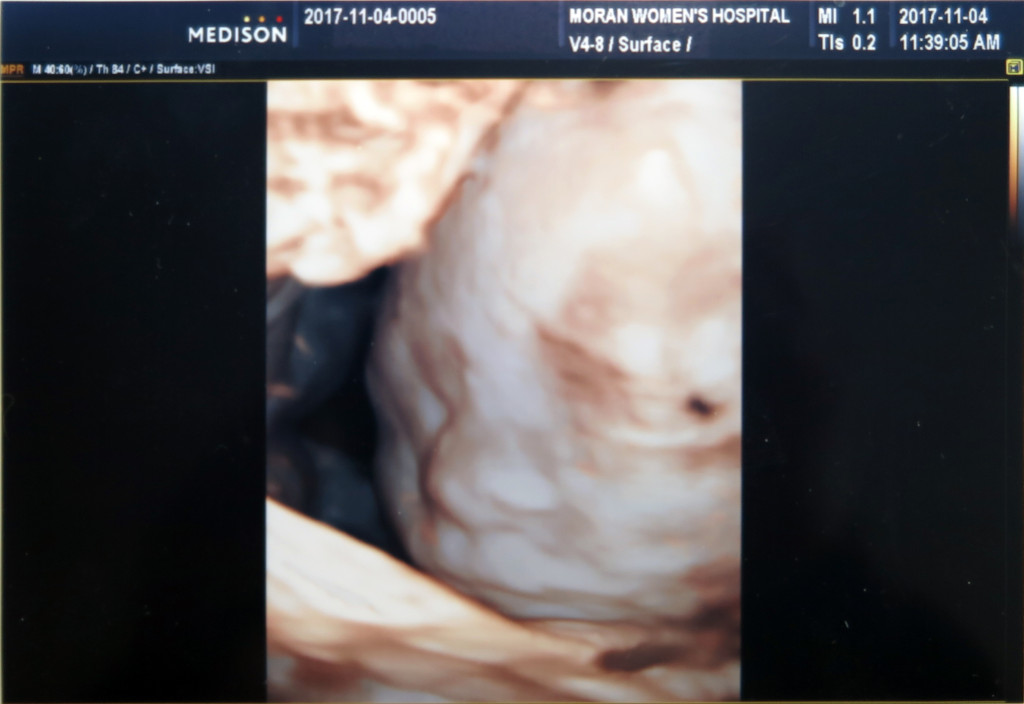

2차 정밀 초음파 사진은 얼굴 윤곽만 살짝 나오네요.

그래도 서현이때 보다 얼굴을 덜 가리고 있어서 이런 해골 사진도 남기고 ㅋㅋ

이때는 서현이랑 얼굴이 많이 비슷해 보이네요 ㅎㅎ

콧대는 서현이 보다는 조금 더 있는듯 하나…

이사진은 잠자는 랑구 표정 판박이네요 ㅋㅋ

가운데 있는게 코고, 밑에 콧구멍 두개가 보입니다^^